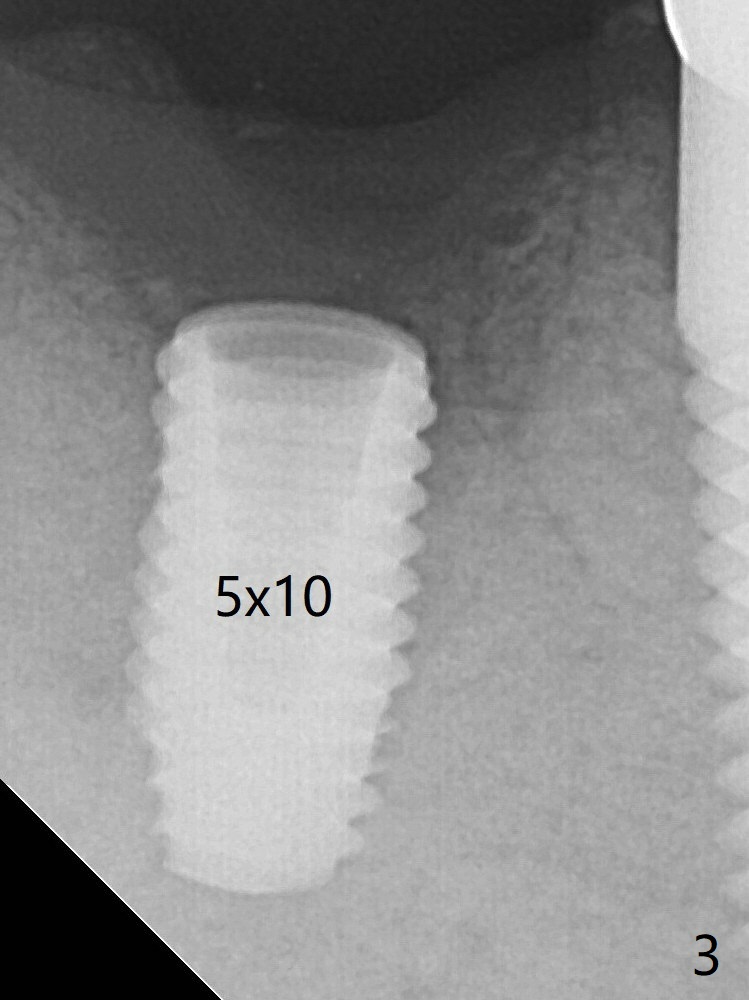

Guided surgery resumes as planned to remove the lingual and apical bone. The buccal bone looks porous from the osteotomy opening. Mixture of autogenous and allograft is packed against the bone plate from the osteotomy before implant placement, but the 5x10 mm implant is unable to be seated completely. After removal of the bone graft from the osteotomy site and use of 4x11.5 mm drill for ~ 1 mm, the implant is seated with ~ 60 Ncm (Fig.3). With buccal incision, bone graft is placed over the distobuccal exposed implant thread (Fig.4 *) following placement of a 6x4 mm healing abutment. The longer healing abutment remains seated (Fig.7 <) without interference from the crest (*) 4.5 months postop. Post-Implant Bone Graft Last Next Xin Wei, DDS, PhD, MS 1st edition 12/23/2019, last revision 01/08/2020